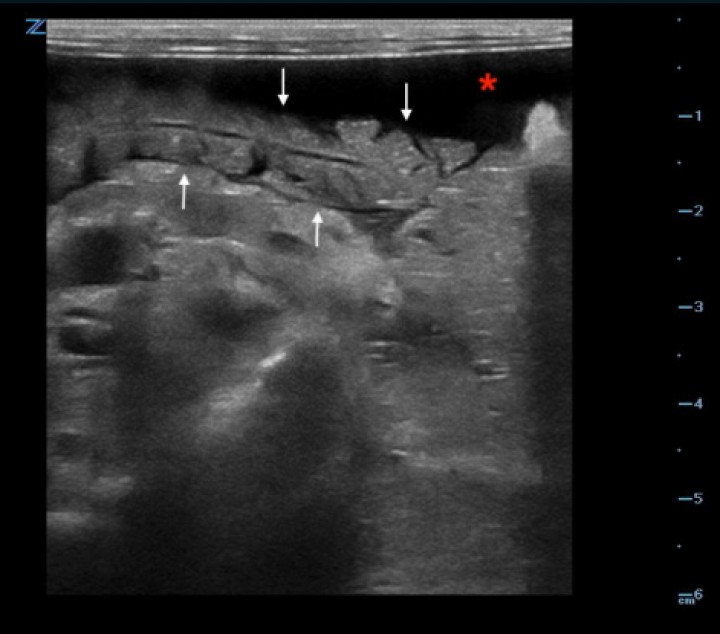

<p>Imagen ecográfica en un corte transversal de la paciente donde se observa el lóbulo pancreático derecho aumentado de volumen con presencia de estrías hipoecoicas compatible con una edematización de la glándula (flechas). Presencia de líquido libre abdominal (*).</p>

Imagen ecográfica en un corte transversal de la paciente donde se observa el lóbulo pancreático derecho aumentado de volumen con presencia de estrías hipoecoicas compatible con una edematización de la glándula (flechas). Presencia de líquido libre abdominal (*).